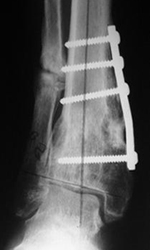

- Artrodesis (fijación articular)

- Prótesis de tobillo.